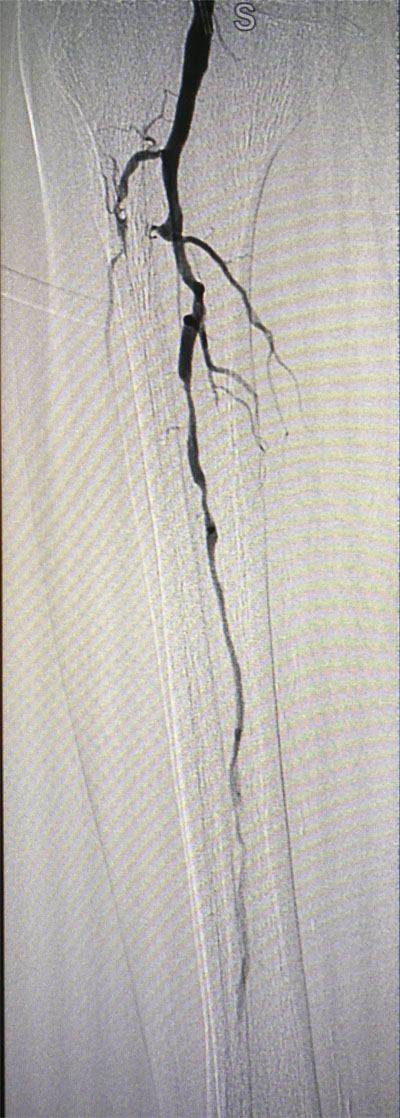

放射科导管室内做好了术前准备,患者由无创呼吸机及各种循环支持下开始介入手术,术中重症监护科严密观察患者的生命体征,内分泌科医生负责手术,患者下肢血流极差,膝下仅存一条多处严重狭窄的腓动脉供血,主要供血的胫前动脉及胫后动脉均长段闭塞,顺行穿刺成功后导丝下行困难,故采用踝下胫后动脉逆穿对接技术成功通过病变。经过近5个小时的奋斗,手术顺利完成,患者腓动脉及胫后动脉血流通畅,血流直达足底动脉环,患者感到足部逐渐温暖,术后清创时患者创面血流丰富。

治疗前